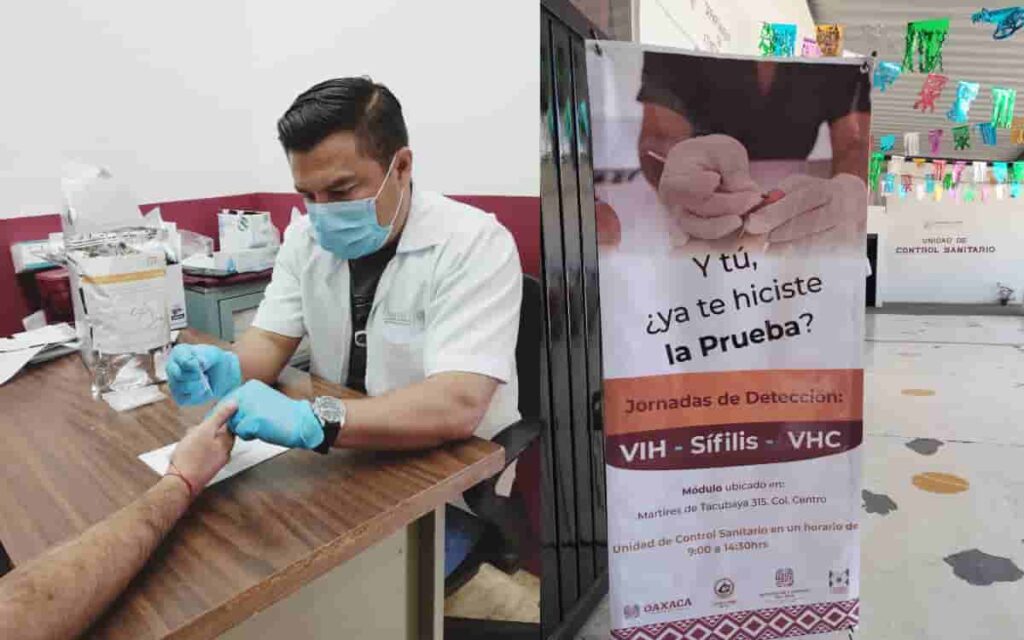

Inauguran unidad móvil de salud en Oaxaca de Juárez para reforzar prevención del VIH, sífilis y hepatitis C

Oaxaca de Juárez, Oax., 31 de julio de 2025.- Con el objetivo de acercar servicios médicos gratuitos a la población, el Consejo Estatal para la Prevención y Control del Sida (Coesida), en coordinación con el Ayuntamiento de Oaxaca de Juárez, puso en marcha una nueva unidad móvil de salud que recorrerá distintas agencias y localidades […]

Casos de VIH-SIDA en aumento en Oaxaca

COESIDA reveló que para 2025, 13 mil personas vivían con VIH y SIDA en nuestro estado.